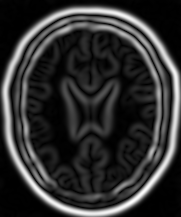

如下图所示阐述了这个滤波器对一个 MRI 脑部图像切片作用的效果,使用的 σ 值分别为 1 ( 左图)、 3 (中图)、 5 (右图)滤波器对一个 MRI 脑部图像切片作用的效果。

输入图像

梯度强度图(σ=1)